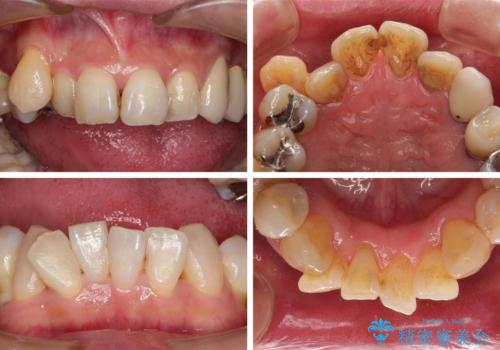

- 歯並びやグラグラする奥歯など、気になる所を全部治したいとのことで来院された患者様です。

奥歯は咬み合わせや歯周病により歯槽骨が失われていたり、むし歯や破折している歯などがあったりと、歯周病治療やインプラント補綴、矯正治療など、総合的に治療が必要と診断されました。

まずは歯周病治療やインプラント埋入を行い、環境が整った後にワイヤーを併用したインビザライン矯正を行い、オールセラミッククラウンにて補綴治療を行うこととしました。

初診時に4年かかりますとお伝えし、実際に4年数ヶ月を要する治療となりました。

治療中は仮歯が頻繁に脱落したり、歯周外科によりむき出しとなった歯根が知覚過敏を起こしたりと、苦労は絶えませんでしたが、4年の治療の後にスッキリと仕上げることができました。